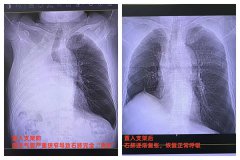

从新疆伊犁到江苏南通,60岁的老杜辗转伊犁、乌鲁木齐、兰州、上海、南通五座城市,跨越四千多公里,直奔他信任的家乡医院南通市第六人民医院,解决困扰他两...